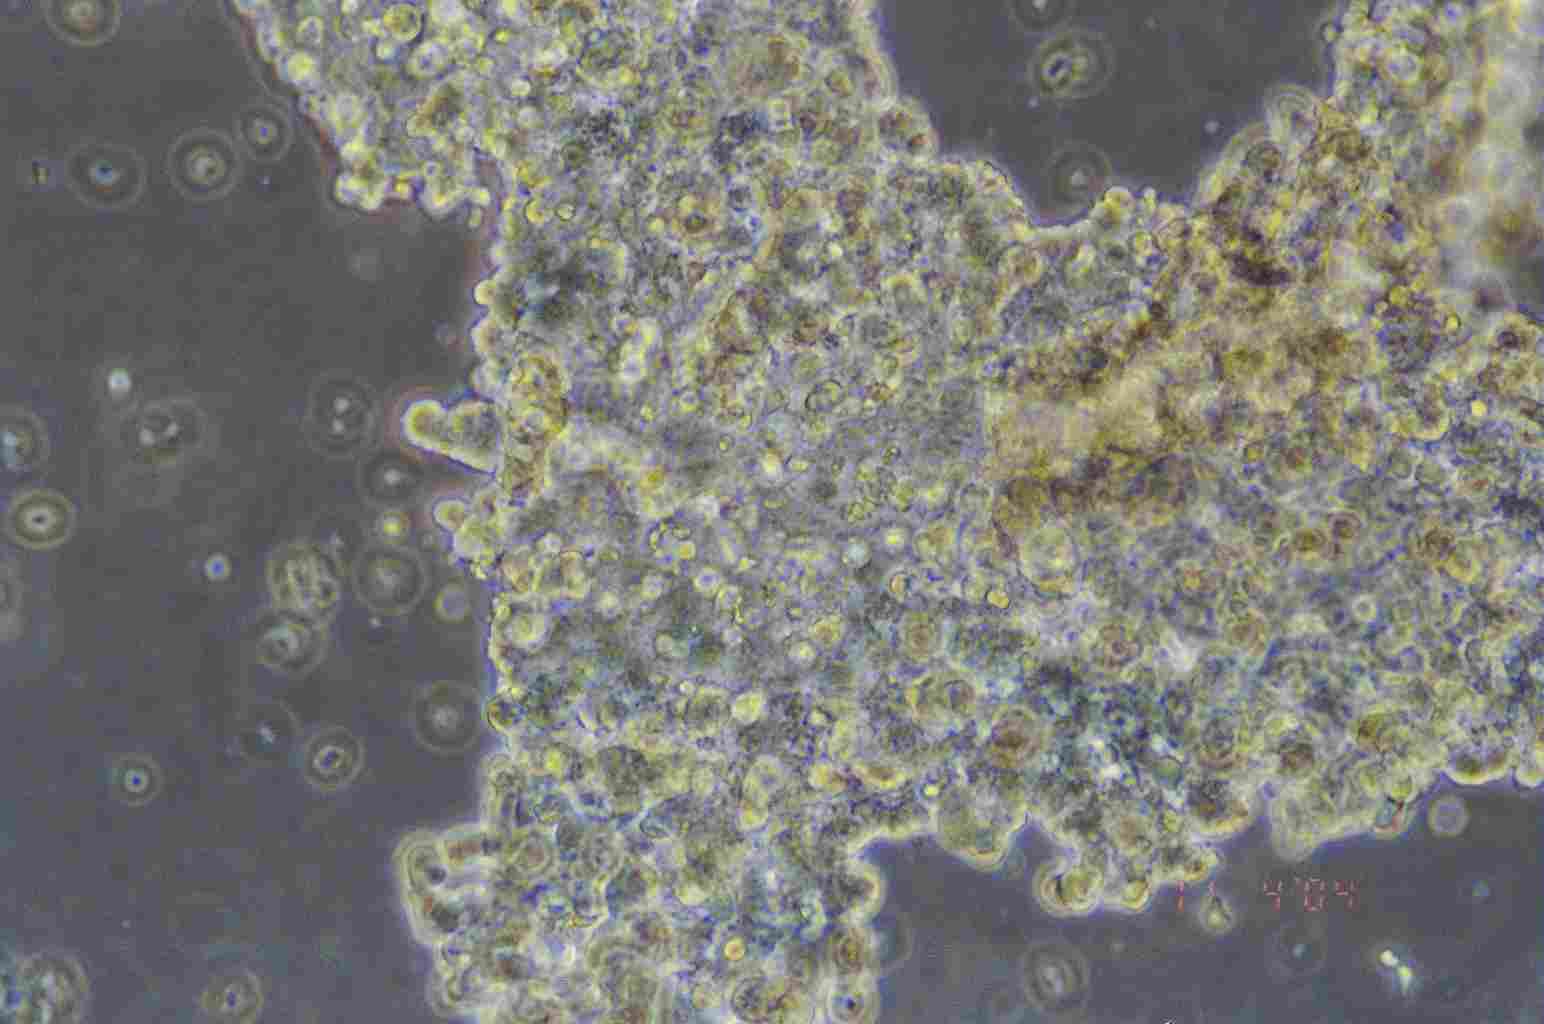

细胞图片:

NCI-H209细胞图片

该细胞由Gazdar AF及其同事于1979年从一名小细胞肺癌患者的骨髓转移灶中分离建立,该骨髓标本的获取先于患者的治疗。该细胞是一种典型的小细胞性肺癌细胞,表达较高水平的4种生化标志:神经特异性烯醇、肌酸激酶脑型同工酶、左旋多巴脱羧酶、铃蟾肽样免疫活性。c-myc DNA序列没有扩增;未发现大的结构DNA的异常;该细胞合成与正常肺相当量的p53 mRNA。该细胞以聚集体的形式悬浮生长,只有聚集体中的细胞是有活力的,但是细胞活率无法估计,一般培养基中含有大量的细胞碎片。该细胞表达异常的RB1蛋白,其706